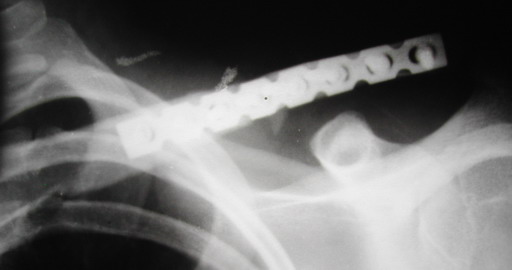

БИОС, пластина, штифт с проволочными петлями, аппарат консольный или комбинация - это решается на уровне местном. Однако в свое время аппарат

Однако, чтобы уснуть с аппаратом внещней фиксации на ключице нужно "устать" не меньше, чем в рамке Чижина. К тому же, у некоторых больных присутсвует страх, что что-то в аппарате может раскрутиться, зацепиться за одеяло или подушку, или воспалиться. Крепко спят пациенты после качественного стабильного погружного остеосинтеза, когда ничего не торчит на коже. Особенно сладко спится после принятия душа или ванны. Это возможно после снятия швов. А вот у "чижиков" и "аппаратчиков" с полноценными водными процедурами определенные трудности.